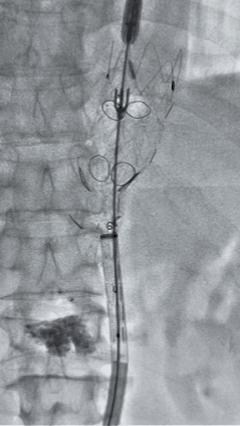

5. 撤出腹腔干导丝导管,经左肱动脉长鞘继续抓捕预置导丝将长鞘超选至另一侧内分支,后超选进肠系膜上动脉,沿导丝送入先健覆膜支架10*100mm一枚,近端重叠内分支,远端重叠于肠系膜上动脉,并予以10mm球囊后扩,手推造影显影良好。

6. 解除束径,打开近端后释放,经肱动脉长鞘超选支架外分支,并进一步超选右侧肾动脉,交换加硬导丝,送入覆膜支架6*50mm和7*60mm各一枚,并予以球囊后扩张,手推造影显影良好。

7. 经长鞘重新选入左侧外分支,并超选进左肾动脉,沿导丝送入外周血管覆膜支架7*60mm一枚,并予以球囊后扩张,手推造影显影良好。